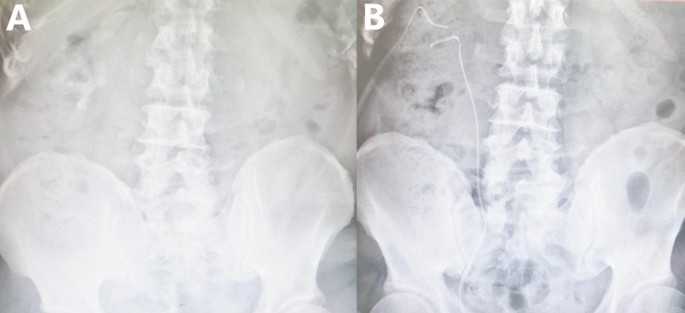

The method of establishing percutaneous renal accesses was similar to that of multi-access MPCNL group, but we will choose a renal calyx that can maximize the clearance of stones. Then the disposable electronic flexible cystoscopy (PC515, Pusen medical, Zhuhai, China) was operated to search and fragment residual stones in the inaccessible locations of nephroscope (mainly beside the PCNL tract insertion) (Fig. 2). At the conclusion of procedure, ultrasound were taken to assess stone clearance. Similarly, a 6 Fr double-J stent and a 14 Fr nephrostomy tube were placed separately. The KUB results of one patient, who has multiple stones, were shown in Fig. 3. During the surgery, a flexible cystoscopy was used to search for residual stones, ultimately achieving complete removal of the stones.

KUB during the perioperative period (A preoperative; B postoperative).